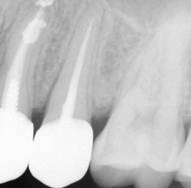

CBCT Scans provide a 3D dental image, while traditional X-rays are only a 2-dimensional picture of the mouth. This means that with traditional X-rays alone, it is very difficult to diagnose non-painful lesions like dental abscesses that are within the jaw bone.

Here are some examples of photos of bone lesions

Patient “A ”Xray of a root canal tooth #14 CBCT Scan of same tooth #14, notice the lesion on the bone at the tip of the left root Notice root canal #13 on xrays CBCT Scan on same tooth #13, there is a lesion at the tip of the root causing sinus membrane inflammation. Patient “C” xray tooth #14 Patient “C” CBCT Scan tooth #14, bone lesion affects both roots. Upland Lighthouse Dentistry, a renowned family dentist in Upland, offers cone beam CBCT scan technology for comprehensive dental care. Our expert dentist utilize this advanced 3D imaging technique to obtain precise details of dental structures, soft tissues, and nerve paths, enhancing our diagnostic accuracy and treatment planning. Contact Upland Lighthouse Dentistry today!